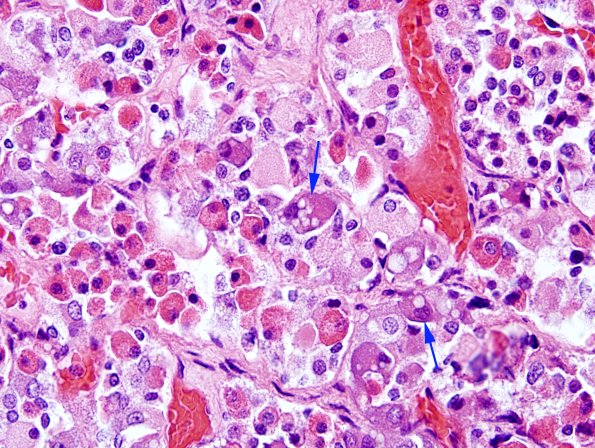

Basophils typically show vacuoles in their cytoplasm (arrows) called enigmatic bodies, which represent complex lysosomes. (H&E)